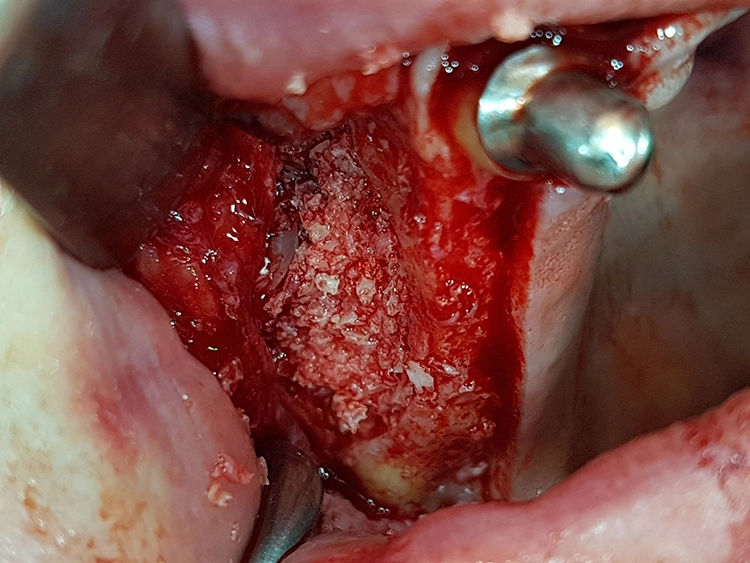

Mit einem Mukoperiostlappen wurden die lateralen Kieferhöhlenwände dargestellt und mittels Piezosurgery beidseitig laterale Fenster präpariert. Der piezochirurgisch abgelöste Knochendeckel ist eine patientenschonende Methode mit vorhersagbarem Ergebnis [4,7].

Bei der Elevation zeigte sich in regio 25 bis 27 eine Mund-Antrum-Verbindung (MAV), verursacht durch den parodontalen Knochenabbau. Da keine Anzeichen für eine Sinusitis vorlagen, wurde die MAV vor dem Verfüllen mit einer resorbierbaren, bovinen Kollagenmembran (Mem-Lok, BioHorizons Camlog) zur Kieferhöhle hin abgedeckt.

Apikal fixiert wurde die Membran durch das Verfüllen des Situs mit autologen Knochenspänen, retromolar aus regio 18 und 28 sowie 38 und 48 entnommen. Diese wurden jeweils zur Hälfte mit allogenem Knochenersatzmaterial (maxgraft, botiss biomaterials, Berlin) gemischt, womit eine natürliche Biofunktionalisierung des Knochenersatzmaterials erreicht wird.

Die präparierten Knochendeckel wurden in einer Kochsalzlösung zwischengelagert, um ein Austrocknen des entnommenen Knochens zu vermeiden. Nach dem Verfüllen konnten die Knochendeckel wieder passgenau in die Fenster repositioniert und das Weichgewebe vernäht werden.

Die Einheilung erfolgte unter der Teleskopprothese. Der Patient wurde darauf hingewiesen, neben der Schonung der Wundfläche und der Verwendung von desinfizierenden Mundspüllösungen sich für zwei bis drei Wochen möglichst nicht zu schnäuzen und zu nießen (Abb. 4-11).